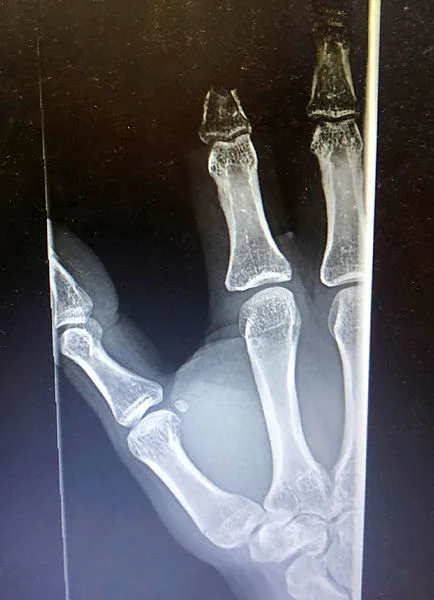

Makine mühendisi Berk Altınelli'nin, geçtiğimiz Şubat'ta yurt dışında açık denizde görevdeyken, kaza sonucu sağ el işaret parmağı orta ekleminden koptu. Helikopterle acilen Malta'da bir hastaneye götürüldü ama doktorlar parmağının dikilmeyeceğini, çöpe atmasını söyledi. Altınelli, pandeminin zor koşullarına rağmen 19 saati bulan film gibi bir operasyonla Türkiye'ye getirildi ve kopan parmağı 11 saat süren bir ameliyatla yerine dikildi.

Parmağından vazgeçmeyen genç mühendis İstanbul'da yaşayan diş hekimi dayısını aradı, bu ameliyatı Türkiye'de yapılıp yapılamayacağını sordu. Annesi Alev Altınelli ile birlikte dayısının da uğraşları sonucu aile rekonstrüktif cerrahi mikrocerrahi alanında çok başarılı ameliyatlar gerçekleştiren Prof. Dr. Mehmet Veli Karaaltın'a ulaştı. Prof. Dr. Karaaltın, normalde uzuv kopmalarında maksimum 8-9 saat içinde uzvun yerine dikilmesi gerektiğini söyleyerek "Risk alıyoruz ama deneyeceğim" dedi. Berk Altınelli'nin neredeyse 24 saati bulan film gibi Malta-Türkiye parmak kurtarma operasyonu bu cümleyle başladı ve literatüre girecek bir ameliyatla genç mühendisin parmağı kurtarıldı.

Literatüre girecek operasyonu gerçekleştiren Estetik, Plastik ve Rekonstrüktif Cerrahi Uzmanı Prof. Dr. Mehmet Veli Karaaltın ise "Süreyi duyar duymaz ilk dediğim şey, olası 8-10 saatlik sınırı epey aştığını, hatta tur döndüğünü, 24 saate kadar uzayabileceğini öğrenince, hastanın yakını olan meslektaşıma 'Deneyeceğiz, başarmaya çalışacağız' dedim sadece. Bazı şeylerin telafisi yok, bir mühendisin işgücü kaybına uğraması çok ciddi bir kayıp. Hem ülke için, hem kendisi için, hem de ailesi için. Bir mühendisin yetişmesi yıllar alıyor. Kitabi bilgiye göre bu kadar süre geçtikten sonra bu ameliyatta başarılı olma ihtimaliniz neredeyse yok. Ben aslında bir risk aldım. Çünkü başarısız olursam, aile anlayışlı baksa da, cerrahi bir başarısızlık olacaktı benim için. Ama hastanın yaşı, konumu yaşayacağı kaybın risklerini düşününce denemeye karar verdim" dedi.

Berk Altınelli'nin çok şanssız bir dönemde böyle bir kaza geçirdiğinin altını çizen Prof. Dr. Karaaltın, "Pandemi var, tarifeli uçuşlar neredeyse yok. Buraya getirilmesi bir hayli zor oldu. Ertesi günü buldu. Tabii ki normal koşullarda ambulans uçak da olabilirdi ama bu şartlar maalesef ona elverişli değildi. 17'nci saatte buraya ulaşabildim" diye konuştu. Uzuv kayıplarında doku ölümünün kansız kalma yani iskemi nedeniyle gerçekleştiğine işaret eden Prof. Dr. Karaaltın, "Parmak, bu açıdan biraz daha dayanıklı bir uzuv. İçinde kas dokusu neredeyse yok. Daha çok bağ dokuları, cilt ve kemik doku var. o açıdan şanslıydık sadece. Bizim yaptığımız ameliyat ise literatüre girecek nitelikte bir operasyon oldu. Çünkü çok uzun bir süre sonra yapılabildi. Berk ameliyattan çıkınca ağladı ve bana sarıldı parmağını kurtarabildiğimiz için. Bu da parmağını kaybetse onda nasıl bir etki oluşacağını (yani aldığımız riske değdiğini) bir kere daha gösterdi" şeklinde konuştu.

"PARMAĞIN KANLANMASI 25'İNCİ SAATTE OLDU"

Yaralanmalarda bazen uzuv kısaltarak organı kurtarmak gerektiğini söyleyen Prof. Dr. Karaaltın, sözlerini şöyle sonlandırdı: "Çünkü azıcık kısa ama işleyen bir parmak olur. Biz o stratejiyi uyguladık. Ama en büyük problem, ezilme ile birlikte kopma yaralanmasıydı. Yurtdışındaki hastanede de parmak replantasyon endikasyonu olmaz demişler. Aslında kitabi olarak doğru. Ama hastanın koşullarına göre bazen risk almak gerekebiliyor. Parmağın kanlanma saati 25 saati buldu. Ben damarı onarıp klempi açıp parmağa kan gideceği zaman duraksadım ve büyük bir heyecanla bekledim. Bakalım parmak, ameliyatımıza cevap verecek mi diye. Klempi açtıktan sonra parmak kanlanınca da çok mutlu oldum. Ameliyatlardan önce saatimi genellikle çıkarır ve masanın üzerine koyarım. Zamanı unuturum. Mikrocerrahi böyle bir şey. Çok heyecanla girdiğim ameliyatlar bunlar. Çünkü uzuv kurtarıyorsunuz. Açıkçası saate bakmadım ama sanırım 11 saati bulmuş. Türkiye, mikrocerrahi açısından bence Avrupa'da en iyi konumda. Şimdiki genç meslektaşlarımız pek istemiyorlar mikrocerrahiyi. Çünkü çok zahmetli ve yorucu. Ama benim onlardan ricam, lütfen bazıları da bu alana girsin. Çünkü ülkenin buna ihtiyacı var"